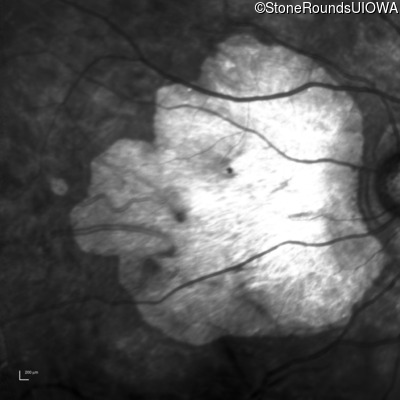

Age at visit: 43 years

OD OS